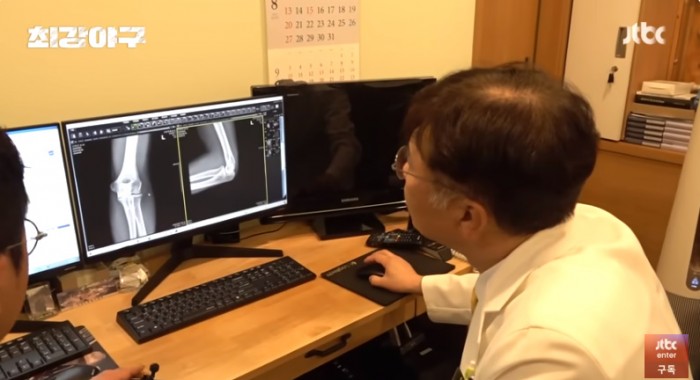

[최강야구] 수술받고도 방출 안 당한 이택근이 진짜 영리하고 대단했던 이유...jpg